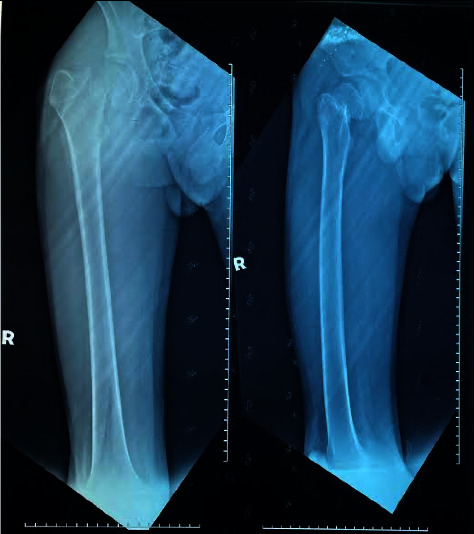

Background: The COVID-19 pandemic has caused major impacts in various aspects of our life. In Malaysia, a Movement Control Order was imposed in March 2020. For almost two years, school going children and adolescents were not able to attend school physically, and their physical activity was confined within their room or house on most days. Case Description. We describe a case of a 14-year-old boy who was previously active in sports and sustained a low trauma fracture at the right neck of the femur following a prolonged period of extreme sedentary life along with poor dietary intake during the COVID-19 pandemic period. He underwent open reduction and screw fixation for the right neck femur fracture. He was thin with a low BMI (15.62 kg/m2) and a significant loss of muscle bulk in all limbs. Laboratory tests showed vitamin D deficiency (15.3 nmol/L) and the dual energy X-ray absorptiometry (DXA) showed a low Z-score for the total spine (-2.2) and total hip (-3.9). He was treated with activated vitamin D and vitamin D3 replacement. Sports physician was involved for individualized postoperative rehabilitation. Successive clinic visits showed remarkable improvements in physical fitness, sports participation, and normalization of vitamin D levels.

Conclusion: A high degree of suspicion is needed to rule out secondary causes in adolescents who present with unusual fragility fractures.